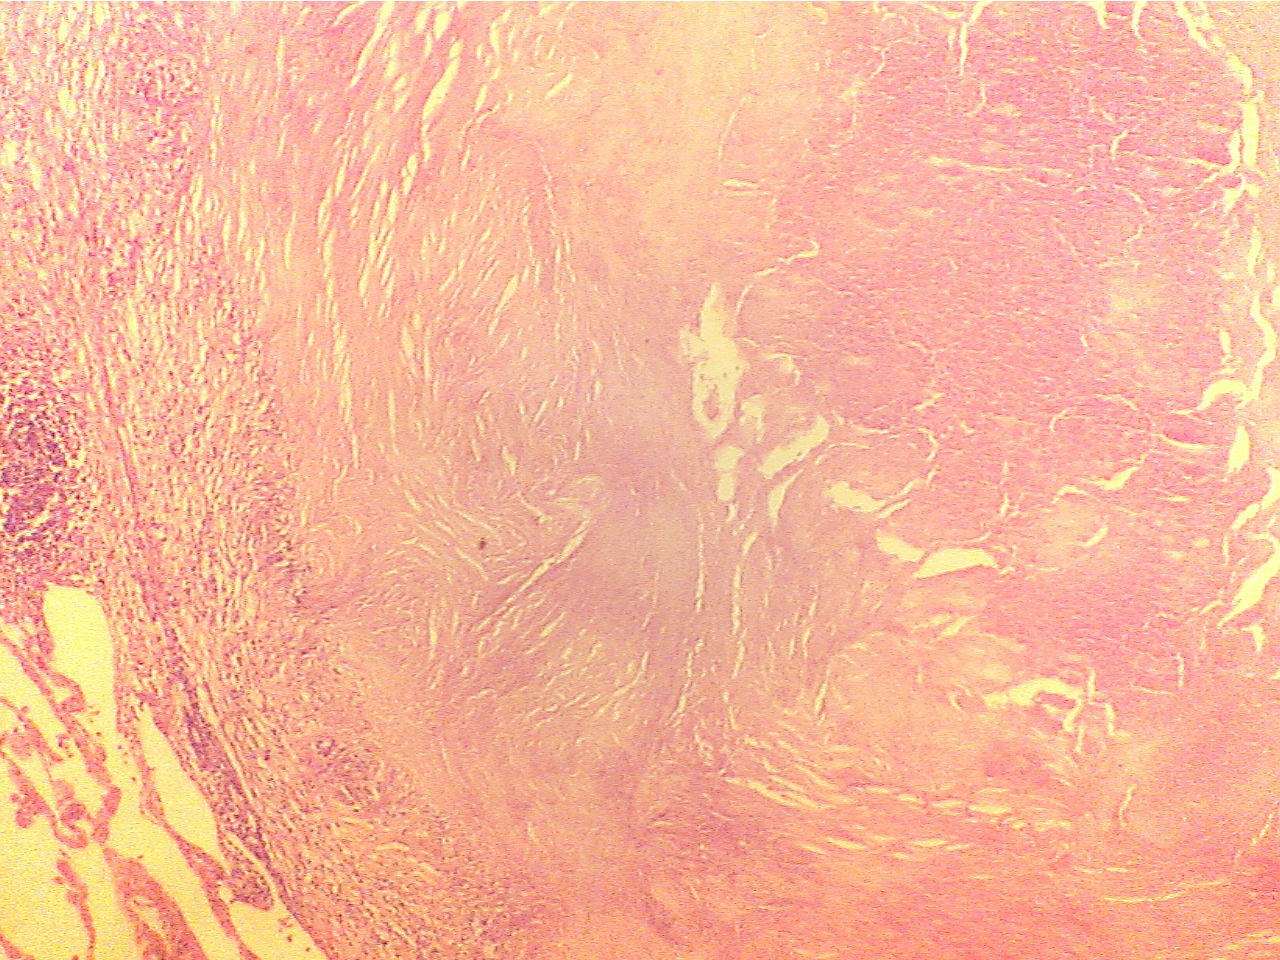

Ghon tubercle - entire (40X1.0)

Ghon tubercle (40X2.0)

Tubercle in center with necrotic core surrounded

by Normal lung (lower

left), capsule (granular and fibrous

capsule, normal lung on extreme left and

right

layers), and core of necrotic material

(center to right edge)